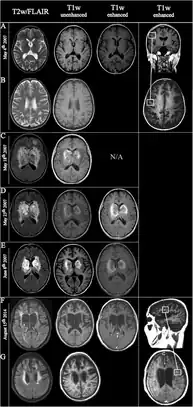

| Fulminating ADEM showing many lesions. The patient survived, but remained in a persistent vegetative state | |